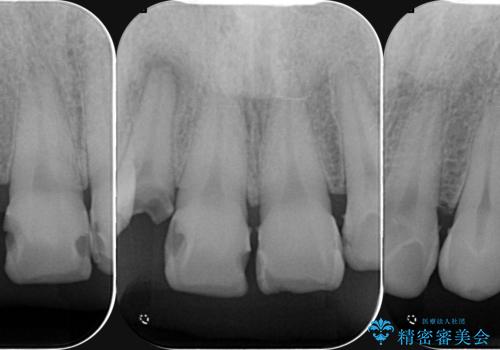

- 前歯の虫歯に気付きながらも放置し、一念発起し治療を希望され来院されました。

虫歯のマイクロスコープによる丁寧な除去、根管治療、深い虫歯に対する挺出(エクストリュージョン)および歯周外科を行ったのち精度の高いセラミッククラウン製作治療を計画します。

虫歯の放置により、根管治療や深い虫歯に対する処置が必要になりましたが丁寧に一つづつ処置を行ったことで抜歯をすることなく歯を残すことができました。